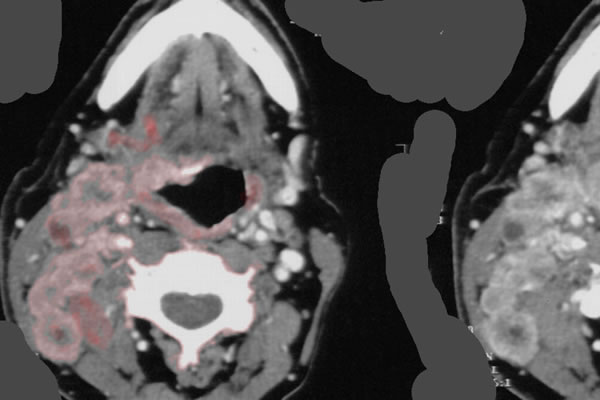

Das CT zeigt ein ausgedehntes Hypopharynxkarzinom mit zervikalen Lymphknotenmetastasen (rosa coloriert).

CT Hypopharynx-Ca